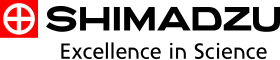

Flex-APS技术,将蒙片像与实时图像之间的变动作为运动矢量,利用每一像素、每一帧计算得出,基于此矢量,在对蒙片像进行了非线性变换后,进行计算,即可对扭曲、弯曲、部分身体移动进行校正。因此,即使用传统的像素偏移处理不能够处理的身体晃动,也能够得到经过充分校正的DSA图像。由于校正处理是实时进行的,因此摄影过程中,所有显示的图像都是通过Flex-APS校正后的DSA 图像。